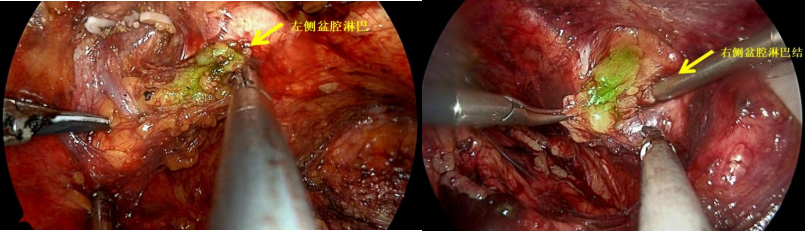

患者为60岁男性,体检时发现PSA升高,指标>100ng/ml。一周后,慕名从浙江至我院浦金贤教授专家门诊就诊。磁共振提示:前列腺中央带腺体及外周带前列腺癌,建议穿刺活检,盆腔左侧淋巴结增大。我院穿刺病理提示:前列腺腺癌,Gleason分级评分4+4=8分,双侧受累。患者PSA升高明显,磁共振下显示盆腔淋巴结肿大,考虑肿瘤负荷较高,预后不佳。浦金贤教授决定行腹腔镜下根治性前列腺切除+盆腔淋巴结清扫术,力求彻底切除肿瘤,提高远期生存。

我院浦金贤教授团队,应用DGPR-1008(一种靶向PSMA的荧光造影剂,目前为临床试验阶段),术前静脉注射,荧光造影剂靶向定位至肿瘤病灶及转移淋巴结位置,多余造影剂经尿液代谢排出体外;术中开启近红外荧光模式后,前列腺癌灶、转移的淋巴结以及肿瘤侵犯转移的其他组织都会因结合了荧光造影剂而产生荧光,使得主刀医生能显著将其与周围正常组织区分开来,进而达到肿瘤彻底、精确、完全的切除。